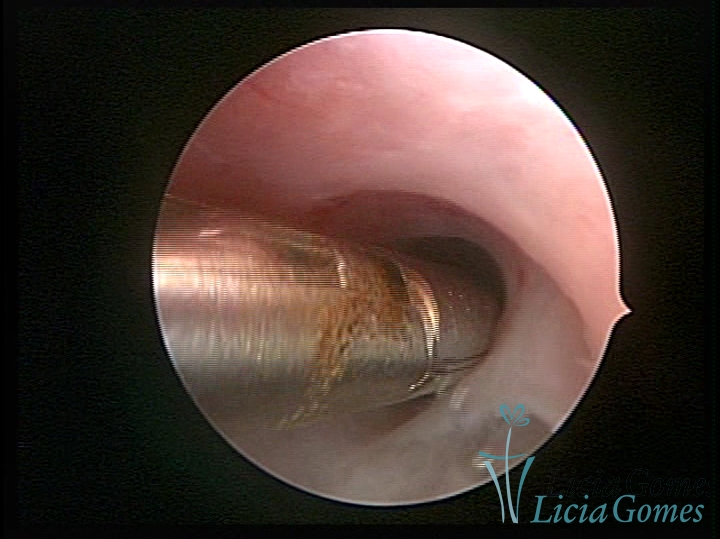

FIBROUS SYNECHIA

• SINÉQUIA TIPO FIBROSA